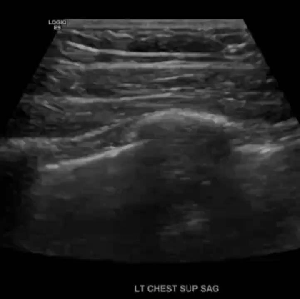

Pleural effusion is a build up of fluid between the layers of the pleura. Scanning subcostally will show fluid above the diaphragm. Scanning intercostally will show fluid anterior the lung. Common causes for pleural effusion is infection, inflammation and malignancy.

The fluid can be anechoic or echogenic in cases of increased exudates, empyema, hemothorax and chylothorax (lymph collection). There may also be septations.